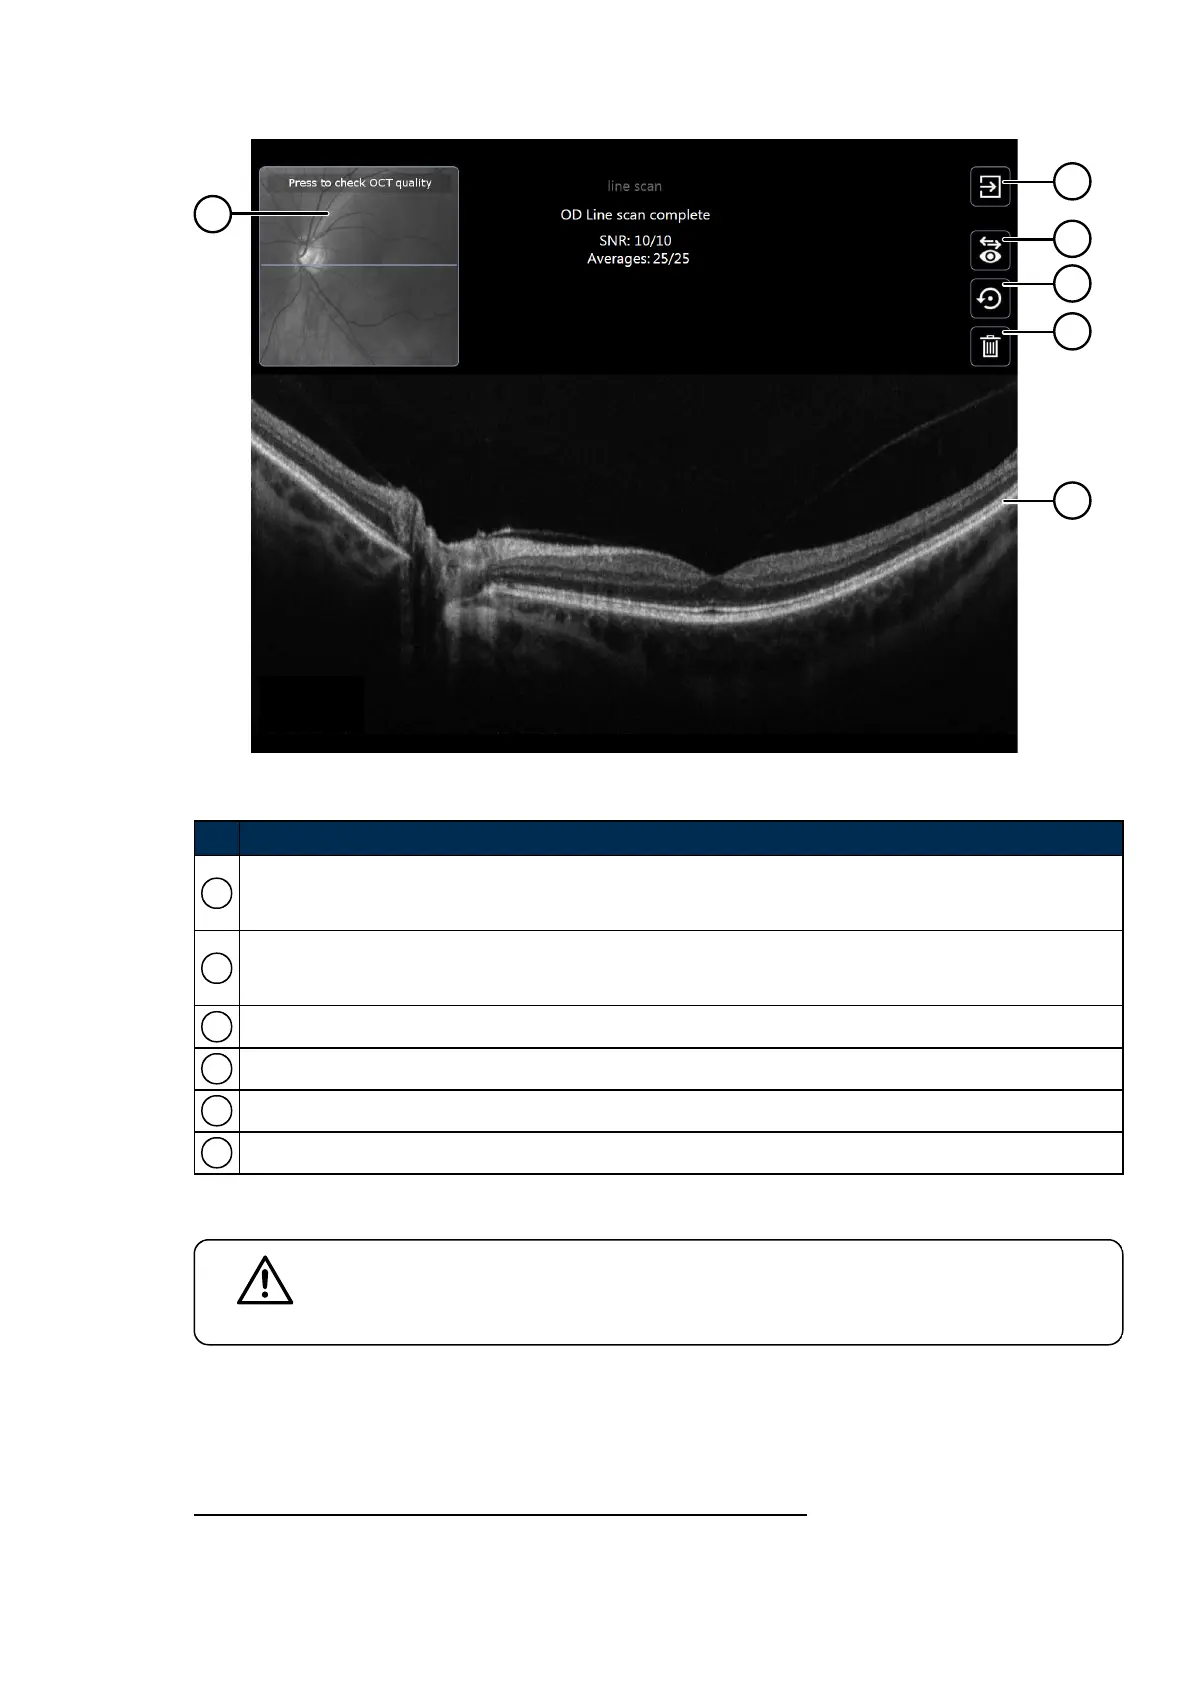

FIGURE 15: OCToptions after capture

No. Description

1

SLO image showing the fundus region corresponding to the OCT scan. Press to check OCT quality.

For topographies, touch the SLO image to replay the OCT frame sequence.

2

Finished OCT.

Returns to the optomap screen to re-align the patient or change the imaging mode.

3 Change the laterality of the captured scan.

4 Save the captured scan and set up to recapture the same scan type.

5 Delete the captured scan and set up to recapture the same scan type.

6 Captured OCTscans.